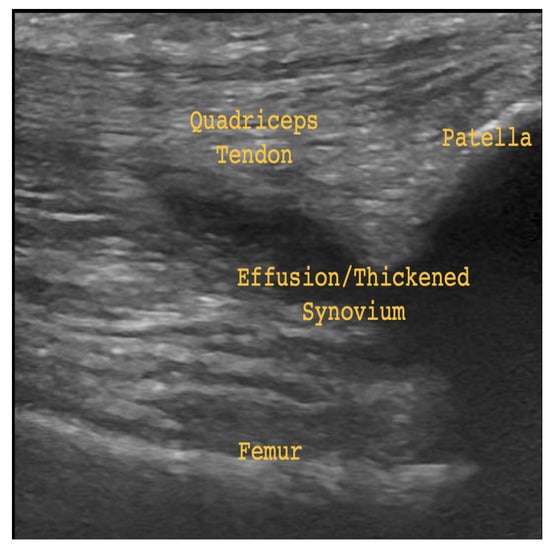

Musculoskeletal ultrasound (MSK-US) is a type of medical imaging used to non-invasively assess the health of bones, muscles, tendons, and ligaments. MSK-US is preferable over alternatives such as magnetic resonance imaging given its lower-cost, bedside point of care, and safety [1]. One prevalent application of MSK-US is the assessment of knee osteoarthritis (OA), a common degenerative joint disease affecting over 25% of adults in the United States [2]. Effusion and thickened synovium have been identified as key indicators of OA, contributors to the disease’s development, and potential targets for its treatment. Effusion refers to the increase of fluid within the joint space. This may cause the joint recess to distend and inflammation (thickening) of the synovial membrane lining the joint space. The latter is known as synovitis, and may lead to further buildup of synovial fluid in the joint space, worsening the effusion [3]. Joint recess distension and thickened synovium may occur together or separately. In Figure 1 some subtle effusion may be discerned by darker patches (echo-free space) in the region labeled Effusion, indicating joint recess distension. In Figure 2, thickened synovium and significantly more effusion may be discerned by the clear presence of echo-free space in the area labeled Effusion/Thickened Synovium. The presence of echo-free space is an indicator of fluid, since the waves emitted by the ultrasound probe are absorbed instead of reflected [3]. Therefore, Figure 2 provides evidence of both joint recess distension and thickened synovium.

The complete MSK-US dataset contained 9987 images of joint recess distension without thickened synovium (negatives), and 1799 images of joint recess distension with thickened synovium (positives). The 9987 negatives belonged to 3800 patients, of whom 180 were children or adolescents, accounting for 310 images. The 1799 positives belonged to 713 patients, of whom 166 were children or adolescents, accounting for 455 images. All images were filtered for the suprapatellar longitudinal view of the knee using a neural network. Of the negatives, 9311 depicted the suprapatellar longitudinal view, while 1651 of the positives depicted the desired view. The suprapatellar longitudinal view is the most appropriate for the diagnosis of recess distension and thickened synovium. Landmarks visible in this view include the patella, quadriceps tendon, and femur. Additionally, the view depicts areas of possible effusion and thickened synovium. See annotations in Figure 1 and Figure 2 for an example. The filtered images were then cropped to remove any annotations in the margins, and their pixel values were normalized to the range [ 1 , 1 ] . See Table 1 for a summary.

Figure 1. Suprapatellar longitudinal view of the knee. Knee joint recess distension in region labeled Effusion. Negative for thickened synovium.

Figure 2. Suprapatellar longitudinal view of the knee. Knee joint recess distension and thickened synovium in region labeled Effusion/Thickened Synovium.